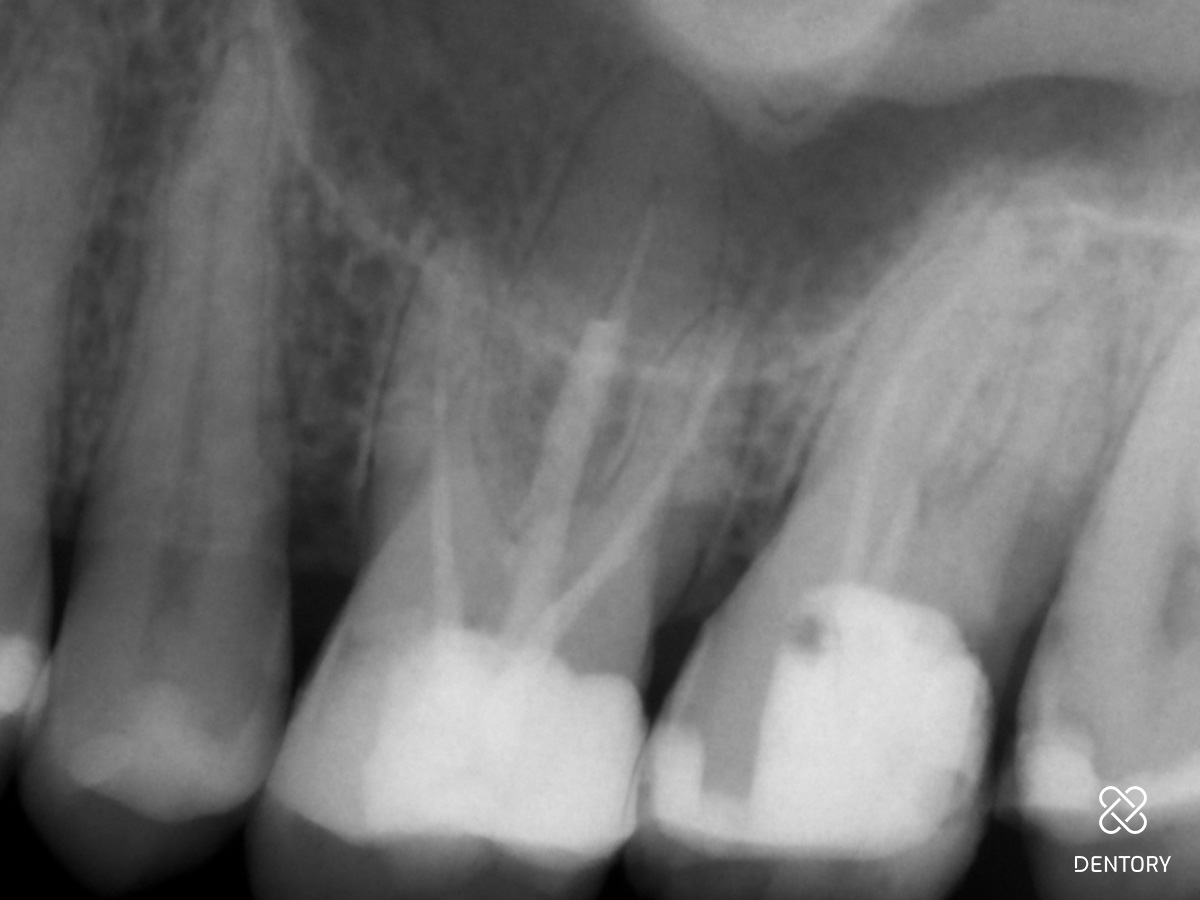

Abbildung 1

Klinische Ausgangssituation.